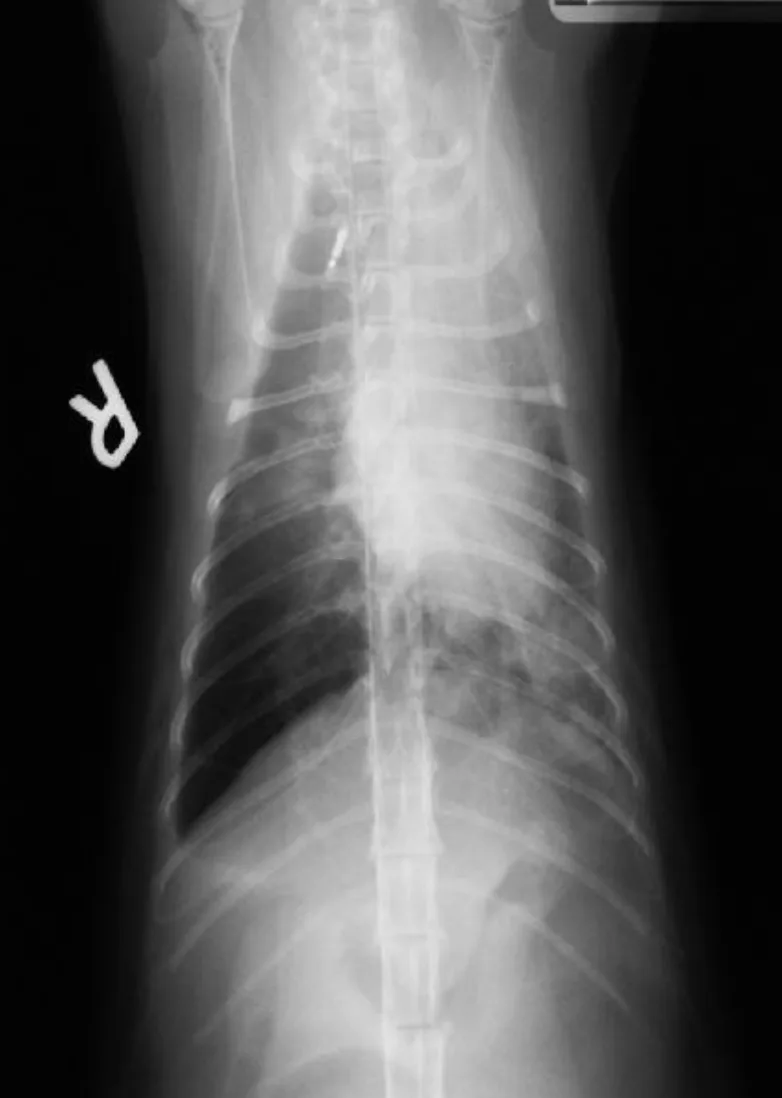

Supportive evidence of heartworm disease may be present on additional diagnostic tests. Although cats are rarely microfilaremic, microfilaria may be detected on a blood smear. Eosinophilia is often transient and rarely identified. Thoracic radiographic findings in cats with heartworm disease include enlarged pulmonary arteries, especially the right caudal lobar artery; bronchointerstitial infiltrate and occasionally pulmonary overinflation, pleural effusion, and pneumothorax may also be present. Radiographic abnormalities may be transient, and right heart enlargement is rarely identified.

Right lateral (A) and dorsoventral (B) thoracic radiographs were taken. Notice the enlarged pulmonary artery (C, arrow) in the dorsoventral view, which provided a clue to her diagnosis.